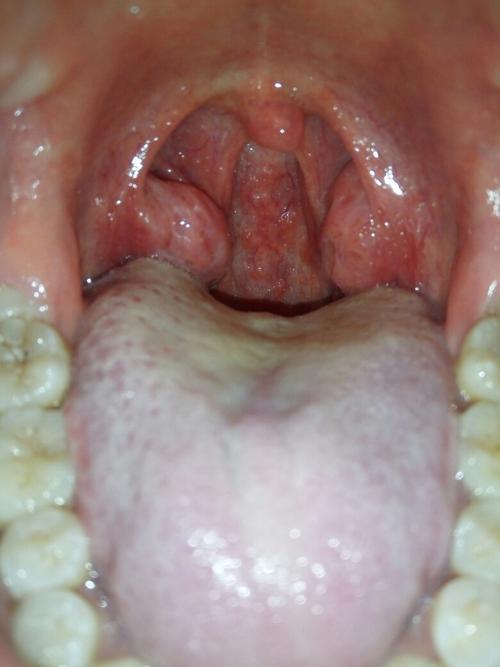

喉咙有泡泡,喉咙长泡泡

喉咙长泡泡

喉咙滤泡

喉咙滤泡图片

喉咙内壁长了很多泡

喉咙内壁长泡图片

喉咙发炎图片

喉咙疱疹图片

喉咙壁上长了好多泡

慢性咽炎喉咙滤泡图片

喉咙长疱疹图片

喉咙正常图片